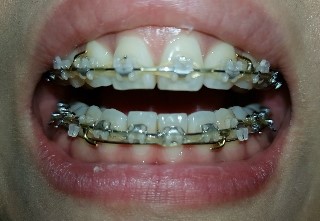

마무리단계

마무리 해도 될거 같다고 하시는데요. 윗니가 아랫니 덮는 정도가 적당한건지 궁금해요. 그리고 아래앞니 두개가 높이가 안맞는데 교정 가능한건가요??

교정마무리 하는데 앞니 교합이 이상합니다

지난8월 비발치교정을하고 얼마전 마무리하자고 하시더니 유지장치까지 달았습니다 그런데 앞니 교합이 안맞는것같아요 휴지를 물면 그냥 빠져나갈정도로 떠있습니다 이대로 장치를 땔까 겁나서요 교정중 저는 고무줄...

우측1,2번 조기접촉때문에 교합조정했는데 그 부분만 휑하니 교합이 들린느낌으로 좌우 교합 밸런스가 안맞아요 ㅜ

돌출입 비발치 교정 9개월차입니다. 3개월차 당기기시작하고 부터 교합이 전체가 계속 안맞음을 느꼈고 하악우측 1~3이 상악보다 덜 들어가서 아랫니가 상악우측 1, 2를 들어올려 들썩들썩하다가 지금으로부터 3주전 ...

교정진행중 마지막단계 부정교합으로 스크류장치설치를했어요ㅜㅜ

선생님안녕하세요~ 걱정이되서 전문의사선생님께 물어보고싶어 글을올려봅니다ㅜㅜ 교정한지이제 이년반다되가구요 거의 일년전에 돌출교정은다끝나고 부정교합때문에 고무줄을걸어야하는 상황인데 제가 타지로 이사...

조언 꼭 부탁드립니다

안녕하세요 저는 교정한지 2년 쫌 넘었구요 교정을 시작한이유는 심한 개방교합과 고르지 못한 치아 때문이였습니다 첫번째 치과에 갔을때 수술을 해야한다 하였고 두번째 치과에서는 수술까지는 필요없다고 하여서 ...

교정중에 과개교합이 왓어요 ㅠ

교정 마무리 단계인데, 과개교합이 왔어요.. 의사샘은 저보고 스크류를 하자고 하는데 사람들 보니깐 스크류 하다가 염증생겨서 다시 뺏다가 심는 사람들도 있고, 정말 심각한 경우는 신경이 손상됐는지 이가 시려하...

교합 마무리 조언 부탁드려요~~~

안녕하세요 위아래 앞니는 이미 교정기도 거의다 뗀 상태고 어금니 쪽에만 교정기가 몇개 남아 있는데 교합 때문에 고민이 많아 매일 잠 못들고 있어서 선생님께 도움 요청 드립니다. ㅠㅠ 일단 첨부한 사진상으로 보...